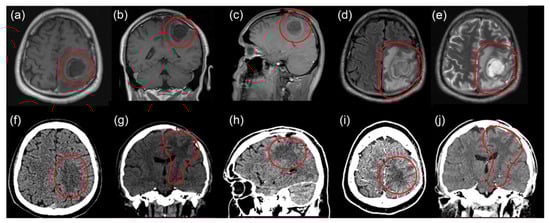

2.3. Third Intervention